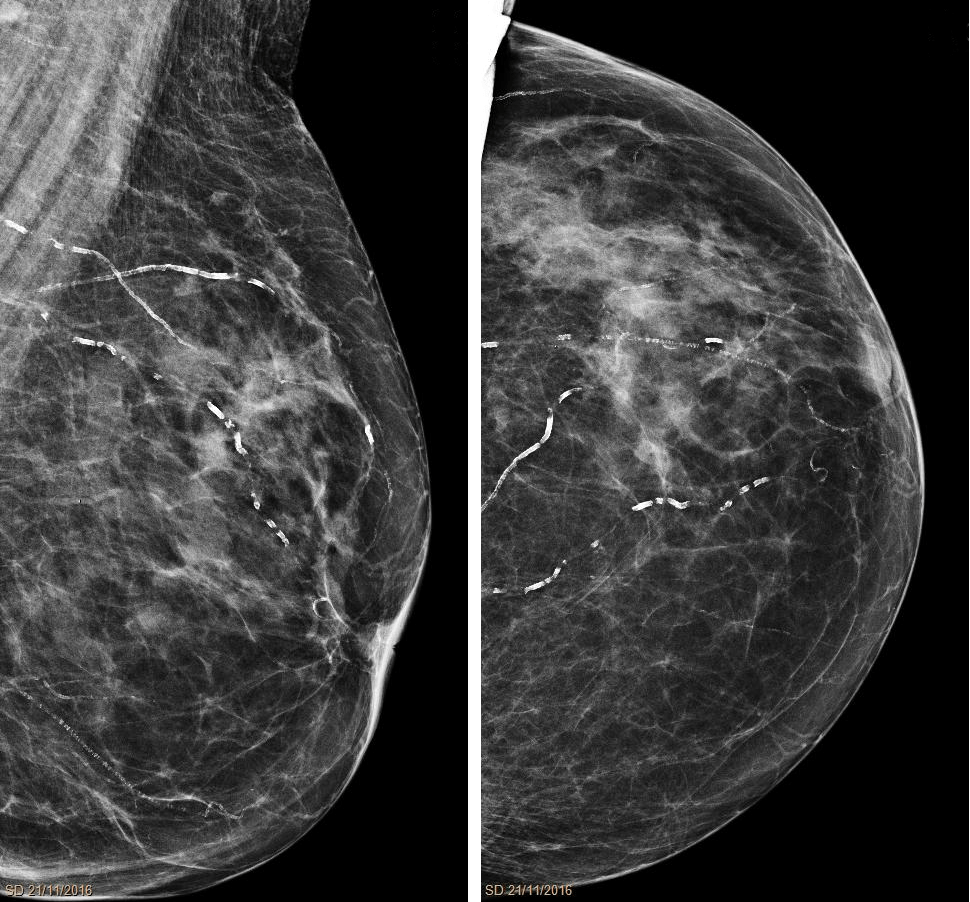

La verdad (desconocida) de las mamografías

Aunque no relacionado a la urología per se, el screening (tamizaje/cribado/detección) del cáncer de mama es un tema controvertido; evidencia relativamente reciente ha mostrado que el screening de cáncer de mama no salva tantas vidas como inicialmente creíamos (fenómeno que ocurre también con el cáncer de próstata, pero eso es un tema para otra ocasión).…